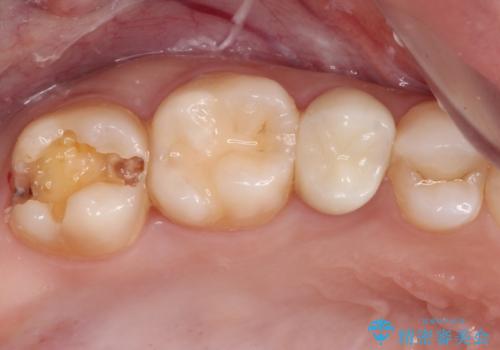

- 近々海外へ転居するとのことで、事前に処置をしておくべきむし歯がないか、気にして来院された患者様です。

レントゲン写真などから、速やかに処置を行うべき歯が2歯あったため、それぞれセラミックインレーとPGAインレー(ゴールドインレー)にて修復治療を行うこととしました。